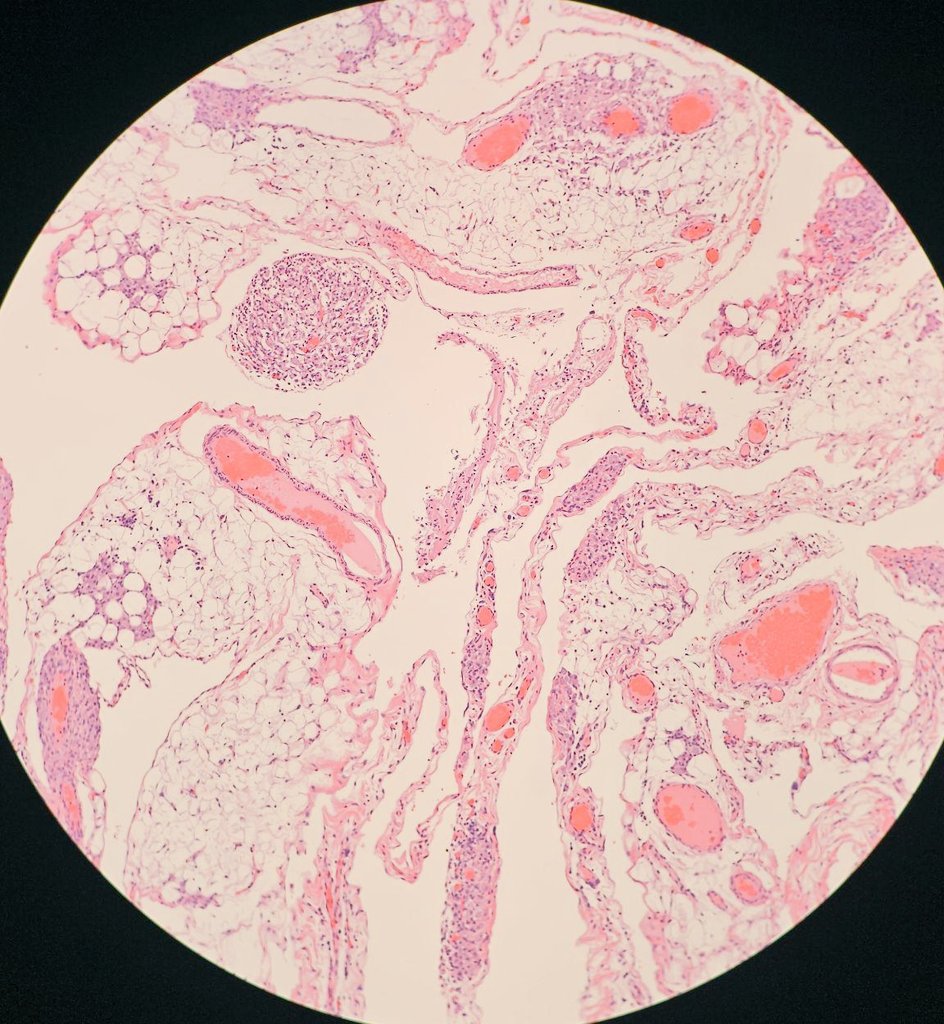

I had only seen this in books, and today, I saw one in person. Nice to meet you, pulmonary hamartoma 😊 #lung #pathology